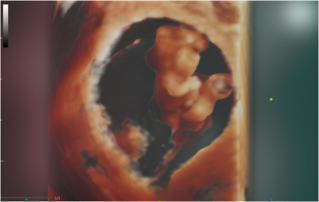

![fetal-body-stalkanomaly-diagnosis.thumb.319.319 Ultrasound Journal 30 - Fetal Body Stalk Anomaly Diagnosis]() Ultrasound Journal 30 - Fetal Body Stalk Anomaly DiagnosisThis prenatal case report showcases the importance of early ultrasound diagnosis for Fetal Body Stalk Anomaly. Follow the journey from initial suspicion to confirmation at 9 weeks using the Mindray Nuewa i9, and understand the prognosis and management implications.Ultrasound Cases | OB GYN | Ultrasound 2024-10-24

Ultrasound Journal 30 - Fetal Body Stalk Anomaly DiagnosisThis prenatal case report showcases the importance of early ultrasound diagnosis for Fetal Body Stalk Anomaly. Follow the journey from initial suspicion to confirmation at 9 weeks using the Mindray Nuewa i9, and understand the prognosis and management implications.Ultrasound Cases | OB GYN | Ultrasound 2024-10-24